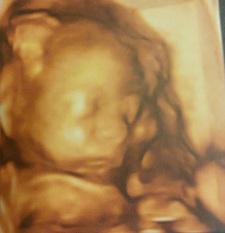

- Ecografia morfológica, donde el ecógrafo comprobará minuciosamente cada uno de los principales órganos del bebé, el saco amniótico y las venas uterinas de la madre (las cuales hacia la semana 24 deben estar “abiertas”, es decir, más gruesas para dejar pasar la sangre necesaria para el bebé).

Aquí teneis a mi retoño durante la ecografía morfológica